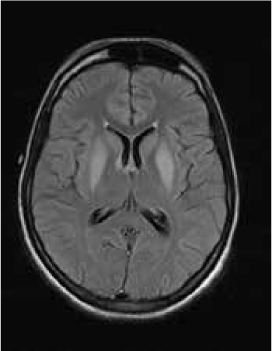

Magnetic resonance imaging (MRI) of the brain showed symmetrically increased T2-weighted and fluid-attenuated inversion recovery signal in the central pons (Figure 1) and in the striatum of the basal ganglia (Figure 2), with no contrast enhancement seen on corresponding T1-weighted postgadolinium images (Figures 3 and 4). Spinal MRI (Figure 5) demonstrated high signal on T2-weighted images from the area postrema in the medulla extending caudally to the T9 thoracic segment, with marked cord swelling and mild enhancement on T1-weighted postcontrast studies (Figure 6), in keeping with a longitudinally extensive inflammatory myelitis.

Postcontrast magnetic resonance image of brain show nonenhancing changes in pons

The clinical and radiologic features supported the diagnosis of NMO. However, the symmetrical pontine and basal ganglia high signal without contrast enhancement were considered to be strongly suggestive of concomitant ODS (pontine and extrapontine myelinolysis).

Neuromyelitis optica may lead to hyponatremia via at least two mechanisms. Area postrema involvement frequently causes intractable vomiting, and this may result in a low serum sodium level. Moreover, the syndrome of inappropriate antidiuretic hormone may develop in patients with NMO and hypothalamic lesions. In the present patient, the lowest recorded sodium level was 132 mmol/L. However, MRI demonstrated features of both central pontine and extrapontine myelinolysis, which, when occurring together, are considered virtually pathognomonic of ODS.4 Typical features include the symmetrical nature of the changes, the involvement of areas typically affected in ODS (pons, basal ganglia), and the sparing of peripheral pontine fibers. However, it remains a possibility that these radiologic changes were due to NMO primarily rather than osmotic demyelination. In a recent review, Kim et al.5 expanded on the range of MRI abnormalities consistent with NMO and NMO spectrum disorders. Gray matter demyelination of the thalamus and bilateral involvement of the corticospinal tracts have been described, although published examples are not as strikingly symmetrical as in this case and do not show the combination of central pontine demyelination with symmetrical striatal involvement.5 To our knowledge, these typical ODS changes in the context of NMO have been described in only one other case, in the Japanese literature.6